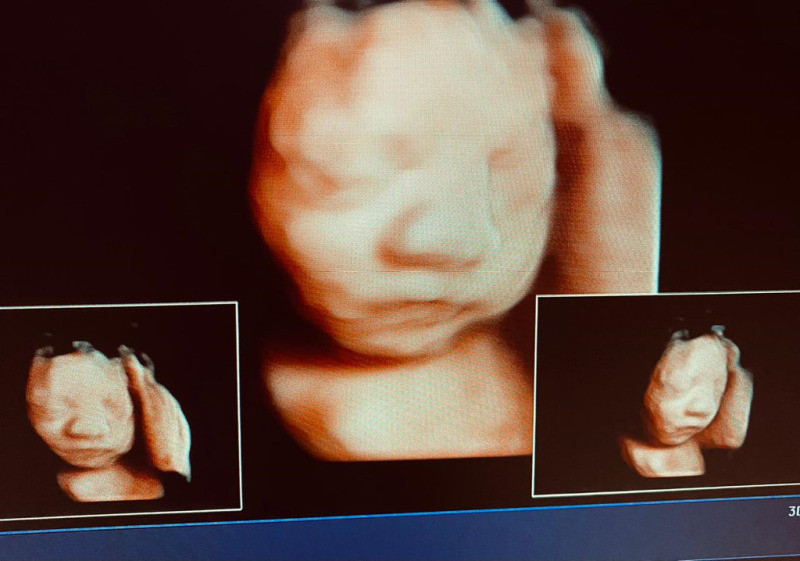

Atención de parto

Envíado por Dra. Erika Lissette Palacios